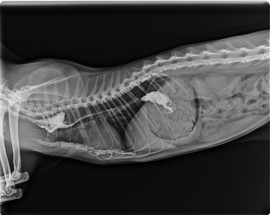

Digitales Röntgen

Diagnostizieren von Erkrankungen des Bewegungsapparates mithilfe einer eingehenden klinischen Untersuchung, digitalen Radiographie und speziellen weiterführenden Untersuchungen.

Anfertigung von HD- und ED-Aufnahmen.